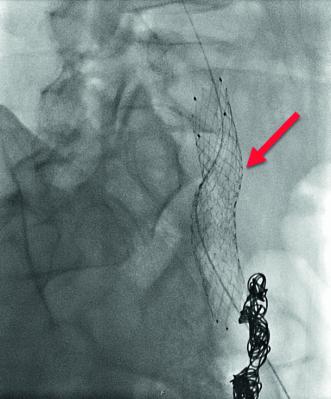

In der klinischen Nachkontrolle drei Wochen später berichtete uns S. B. von einer massiven Besserung der Unterbauchbeschwerden. In der Laufbanduntersuchung liessen sich jedoch noch belastungsabhängige Beschwerden im linken Bein provozieren, wonach auf Wunsch von der Patientin eine ergänzende Sanierung der May-Thurner-Läsion beschlossen wurde. In einer zweiten kathetertechnischen Intervention erfolgte von femoral eine Stent-Implantation in der Vena iliaca communis links (Abb. 8). Wir behielten die Patientin zur Überwachung der Vitalparameter eine Nacht hospitalisiert. Die Patientin ist nach einer jahrelangen Schmerzanamnese vollständig beschwerdefrei geworden.

Die Behandlungsmöglichkeiten des Pelvic Congestion Syndroms sind vielversprechend. Bei gefestigter Diagnose beträgt die Erfolgsquote der kathetertechnischen Therapie über 80 %. Entscheidend für den Therapieerfolg ist die vorgängige Abklärung von obstruierenden venösen Anomalien. Beim Nachweis von Obstruktionen der Beckenvenen oder Vena cava ist die kathetertechnische Embolisation mittels Schaumsklerosierung und Coiling alleine nicht ausreichend, um das Beschwerdebild nachhaltig zu verbessern. Erforderlich ist die Dekompression mittels Stent-Implantation, was bestenfalls im gleichen Eingriff vorgenommen werden kann.